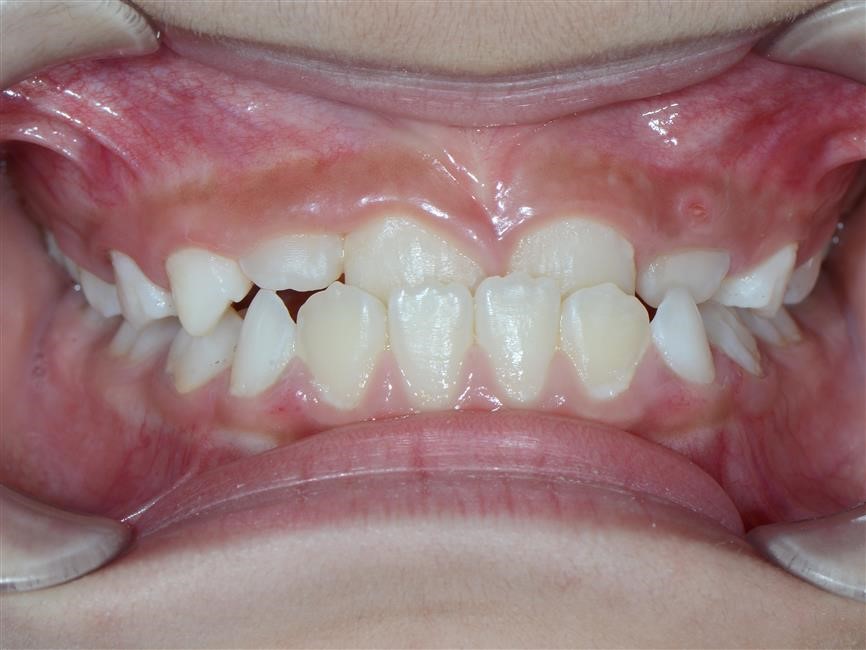

Vậy như thế nào là khớp cắn bình thường và khớp cắn lệch lạc? Đáng ngạc nhiên là không chỉ đơn thuần có một câu trả lời. Một khớp cắn bình thường được mô tả bằng những tiêu chí như: lý tưởng, phù hợp giải phẫu, mang tính trung bình, mang tính thẩm mỹ, hợp lý, đảm bảo chức năng cắn và khớp cắn không ảnh hưởng tới sức khỏe răng miệng. Do vậy, trên thực tế, cùng một vấn đề nhưng có thể có tồn tại nhiều hướng giải quyết khác nhau: điều trị hay không điều trị. Lệch lạc khớp cắn không phải là một bệnh nhưng là một biến thể khác so với tình trạng bình thường và có thể ảnh hưởng không tốt đến tình trạng sức khỏe răng miệng nói chung. Về cơ bản, có ba nguyên nhân chính dẫn tới việc cần phải tiến hành chỉnh nha: 1- Tình trạng, khấp khểnh, vẩu răng-hàm 2- Điều chỉnh chức năng ăn nhai của răng 3- Loại bỏ các nguy cơ có thể gây tổn hại tới sự khỏe mạnh lâu dài của răng và mô quanh răng.

Chức năng cắn: Những răng không được tiếp xúc tốt với răng tương ứng ở hàm đối diện có thể gây khó khăn khi ăn uống và có thể dẫn tới rối loạn chức năng khớp thái dương- hàm. Tuy nhiên, mối liên hệ giữa rối loạn chức năng khớp thái dương hàm và lệch lạc khớp cắn vẫn là một vấn đề gây tranh cãi. Những cá nhân có khớp cắn không tốt, có thể cảm thấy khó khăn và ngượng ngùng khi ăn vì họ không thể cắn được miếng thức ăn bằng răng cửa của mình. Họ chỉ có thể nhai thức ăn bằng những răng phía sau. Sức khỏe răng miệng: Vệ sinh răng miệng trở nên khó khăn hơn. răng dễ có mảng bám và cao răng hơn nếu hàm răng khấp khểnh không đều. Do vậy, bệnh nhân có thể dễ bị sâu răng và các bệnh nha chu khác như viêm lợi và viêm quanh răng hơn. Tuy nhiên, nếu có một hàm răng đều đặn mà không có ý thức và thực hành vệ sinh răng miệng tốt thì cũng không thể có tình trạng vệ sinh răng miệng tốt. Nếu chải răng không đầy đủ và không đúng cách, các bệnh nha chu sẽ tiến triển bất chấp hàm răng của họ thẳng đều đến mức nào. Trong nhiều trường hợp lệch lạc khớp cắn có thể làm tổn thương cả răng và mô mềm nếu không được điều trị. Hiển nhiên rằng răng cửa hàm trên càng chìa ra nhiều bao nhiêu thì nó lại càng dễ bị tổn thương bấy nhiêu. Khi khoảng cách theo chiều ngang giữa răng cửa hàm trên và răng cửa hàm dưới là 9mm hoặc lớn hơn, nguy cơ tổn thương răng cửa hàm trên tăng lên tới hơn 40%. Giảm độ chìa ra của răng cửa hàm trên không chỉ có lợi ích trên quan điểm thẩm mỹ mà còn hạn chế tối đa nguy cơ chấn thương và sự phức tạp về lâu về dài cho cả hàm răng. Những tình trạng khớp cắn ngược, không chỉ ảnh hưởng nhiều đến vấn đề thẩm mỹ mà còn ảnh hưởng đến chức năng cắn và gây ra tình trạng mòn răng – răng sớm, răng cửa dưới bị tiêu xương ổ răng, lợi bị co…Trong trường hợp được điều trị sớm, tổn thương mô mềm sẽ dừng lại và khi phần lợi còn lại được tái tạo thì tình trạng sẽ được cải thiện một cách tự nhiên và không để lại vấn đề gì sau này.